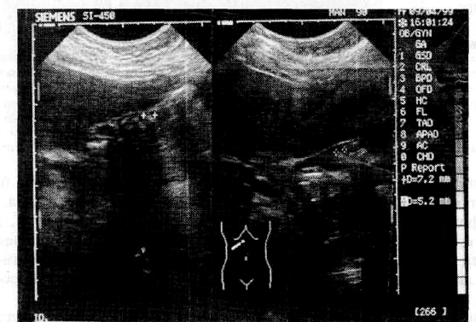

В результате проведения курсов Литолизина по обычной схеме наступила ремиссия желчнокаменной болезни: исчезли боли, запоры, отрыжка, пропало чувство горечи во рту, расширилась диета, повысилась работоспособность и улучшилось качество жизни. Но только через 2 года в апреле 1999 г. на УЗИ зарегистрировано размягчение, разбухание мелких камней и увеличение их размеров до 7 мм. В результате этого камни стали взвешенными, т.е. плавающими, а полость уже на 2/3 заполнилась камнями, увеличившими свой размер почти вдвое. Диагноз: желчнокаменная болезнь

Рис. 6а. До лечения. Желчный пузырь не увеличен, стенки уплотнены, в просвете (до 4 мм) множественные мелкие неподвижные плотные конкременты. (1/3 объема желчного пузыря). Заключение: ЖКБ. Хр. калъкулезный холецистит. 22.04.97.

Рис. 6б. После 2-летнего приема Литолизина. Желчный пузырь гипотоничен 59x16 мм, стенки 2,4мм. В полости взвешенные конкременты до 7мм, занимают 2/3 объема.

Заключение: ЖКБ. 09.04.99.